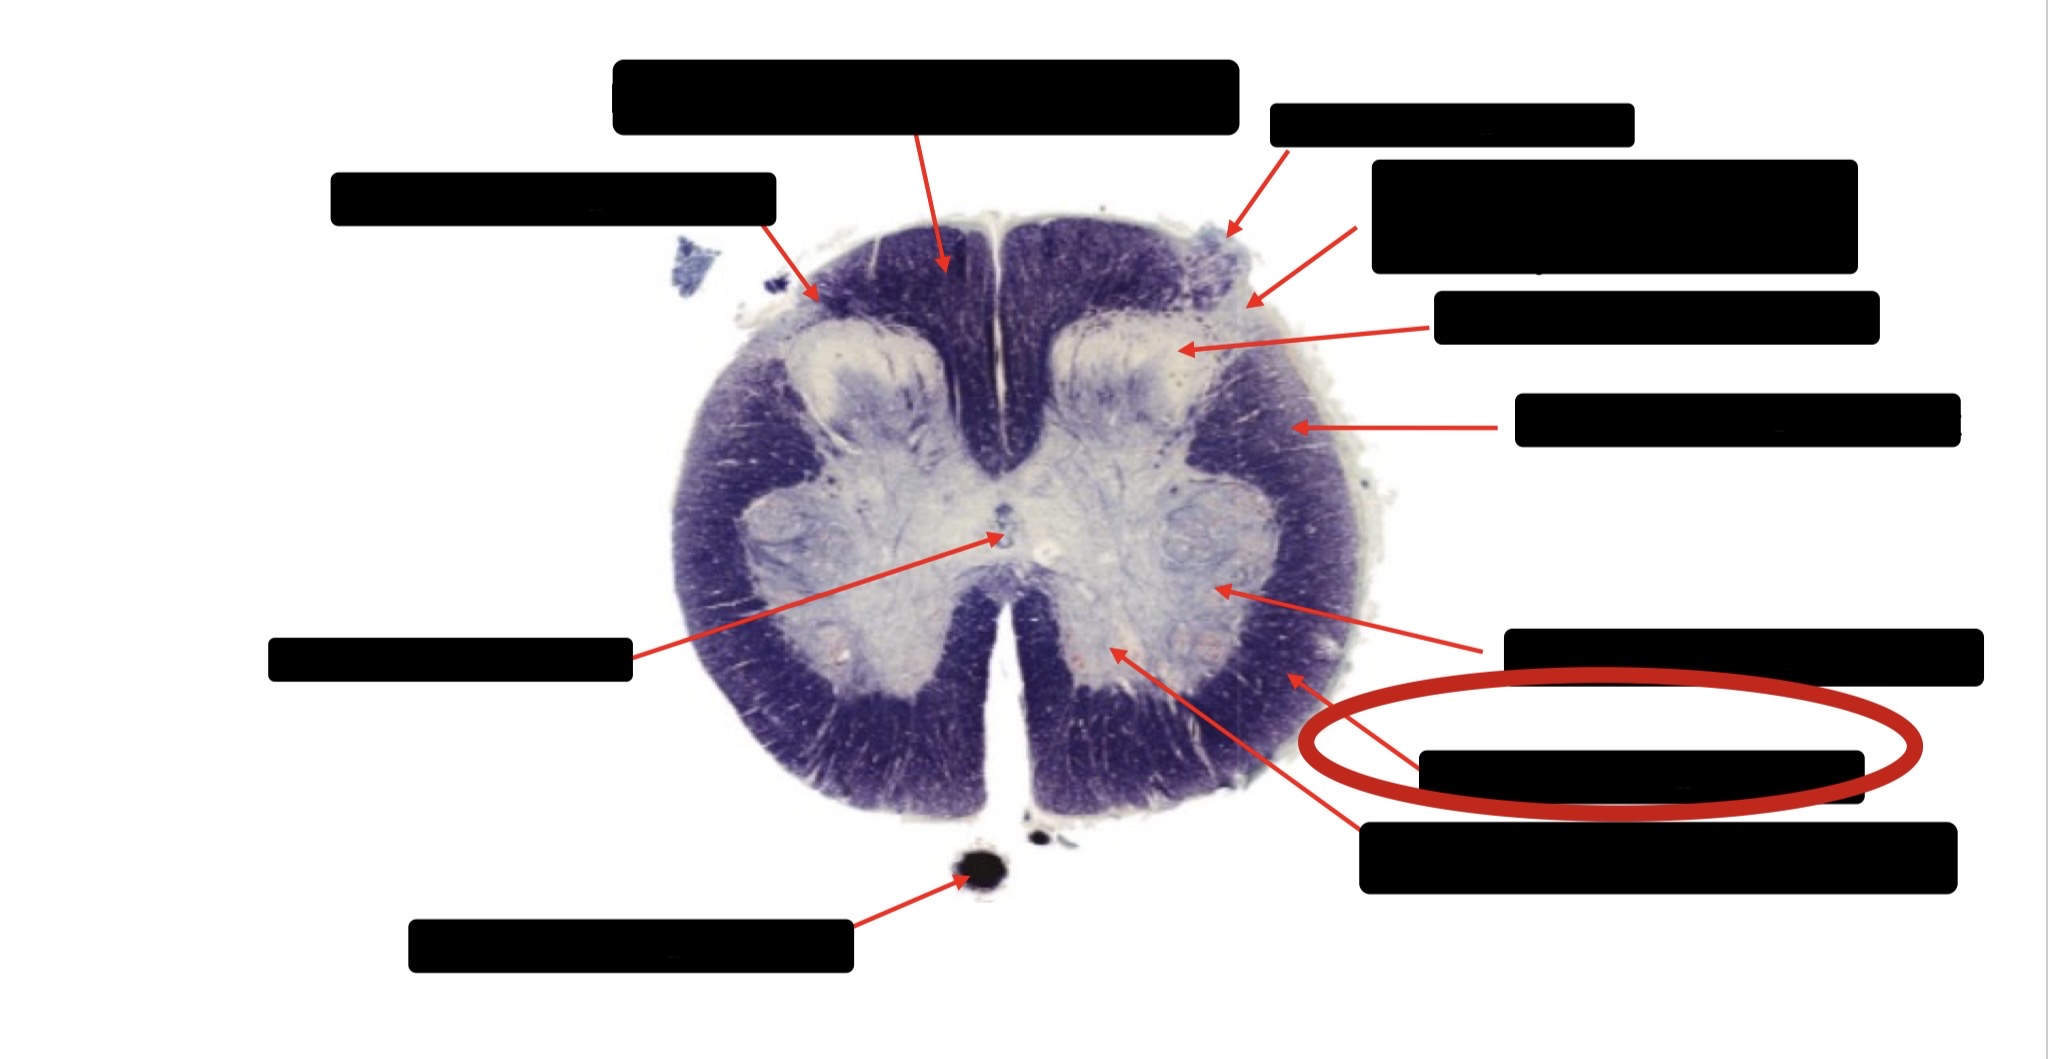

Posterior Column

Large Fiber Entry Zone

Posterior Spinocerebellar Tract

Clarke’s Nucleus

Anterior Spinocerebellar Tract

Ventral Root Fibers

Central Canal

Lissauer’s Tract & Small Fiber Entry Zone

Substantia Gelatinosa

Lateral Corticospinal Tract

Spinothalamic Tract

Anterior Horn Motor Neurons (Distal Muscles)

Anterior Horn Motor Neurons (Proximal Muscles)

Dorsal Rootlet

Lateral Horn